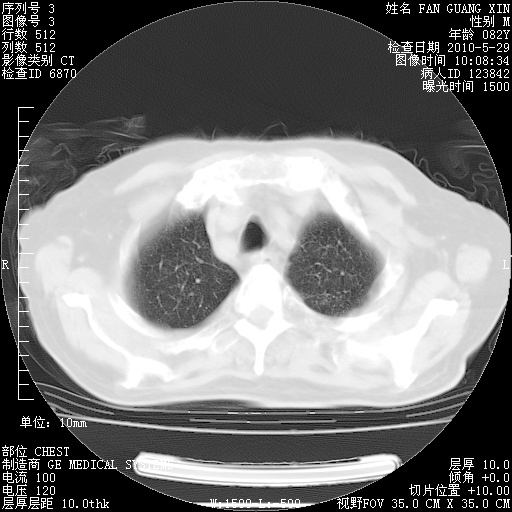

再治疗10天后的肺部CT

再治疗10天后的肺部CT 纵膈窗

肺部体征:呼吸25次/分,心率100次/分,呼吸音增粗。无干湿罗音。

从白细胞总数和中性比例看好像合并感染。肺部纹理好像比上次多,支气管炎?其他感染?

阅读此次胸部CT,肺间质渗出性改变较入院时有吸收。目前从体温、白细胞、中性分叶明显增高,肯定存在细菌感染(发生医院感染哦,若无消化道及泌尿系统等感染的依据,肺部感染可能大)。若你院头孢哌酮舒巴坦钠耐药率较高,同意你的方案,若48小时体温仍高,可考虑使用碳青霉稀类抗菌药物,同时可予超声雾化、注意滴数时加大液体量。白蛋白33.30g/L较低哦,需加强营养等支持治疗。